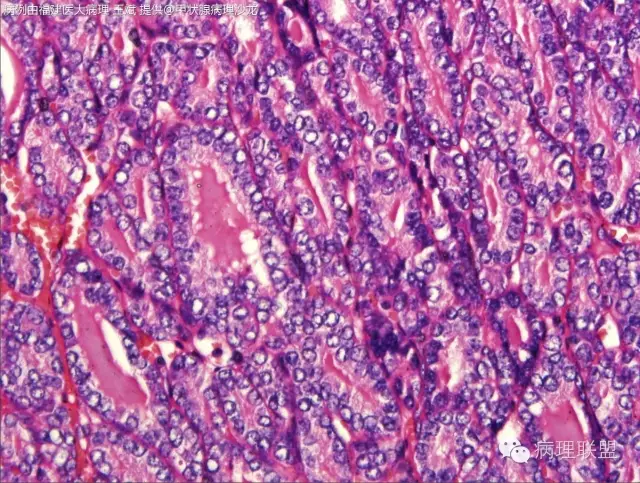

女性,20岁,甲状腺肿物(本病例由福建医大病理 王斌提供,致谢!)

Encapsulated follicular variant papillary thyroid carcinoma with capsular invasion——如总体为包裹性滤泡性病变的话(图一提示,但只一部分)

核的特征不明确,是不是得考虑滤泡癌。

滤泡癌和滤泡亚型PTC预后及治疗有何区别?韩帅,我觉得核的特征还是有的@河南新密人医病理科韩峰楼

有少量核沟,如果核够就是滤泡亚型ptc

此片中所显示的“核特征”为人工现象,滤泡癌。

@福建医大病理 王斌 这种生长方式就是癌,无论免疫组化如何表达或不表达